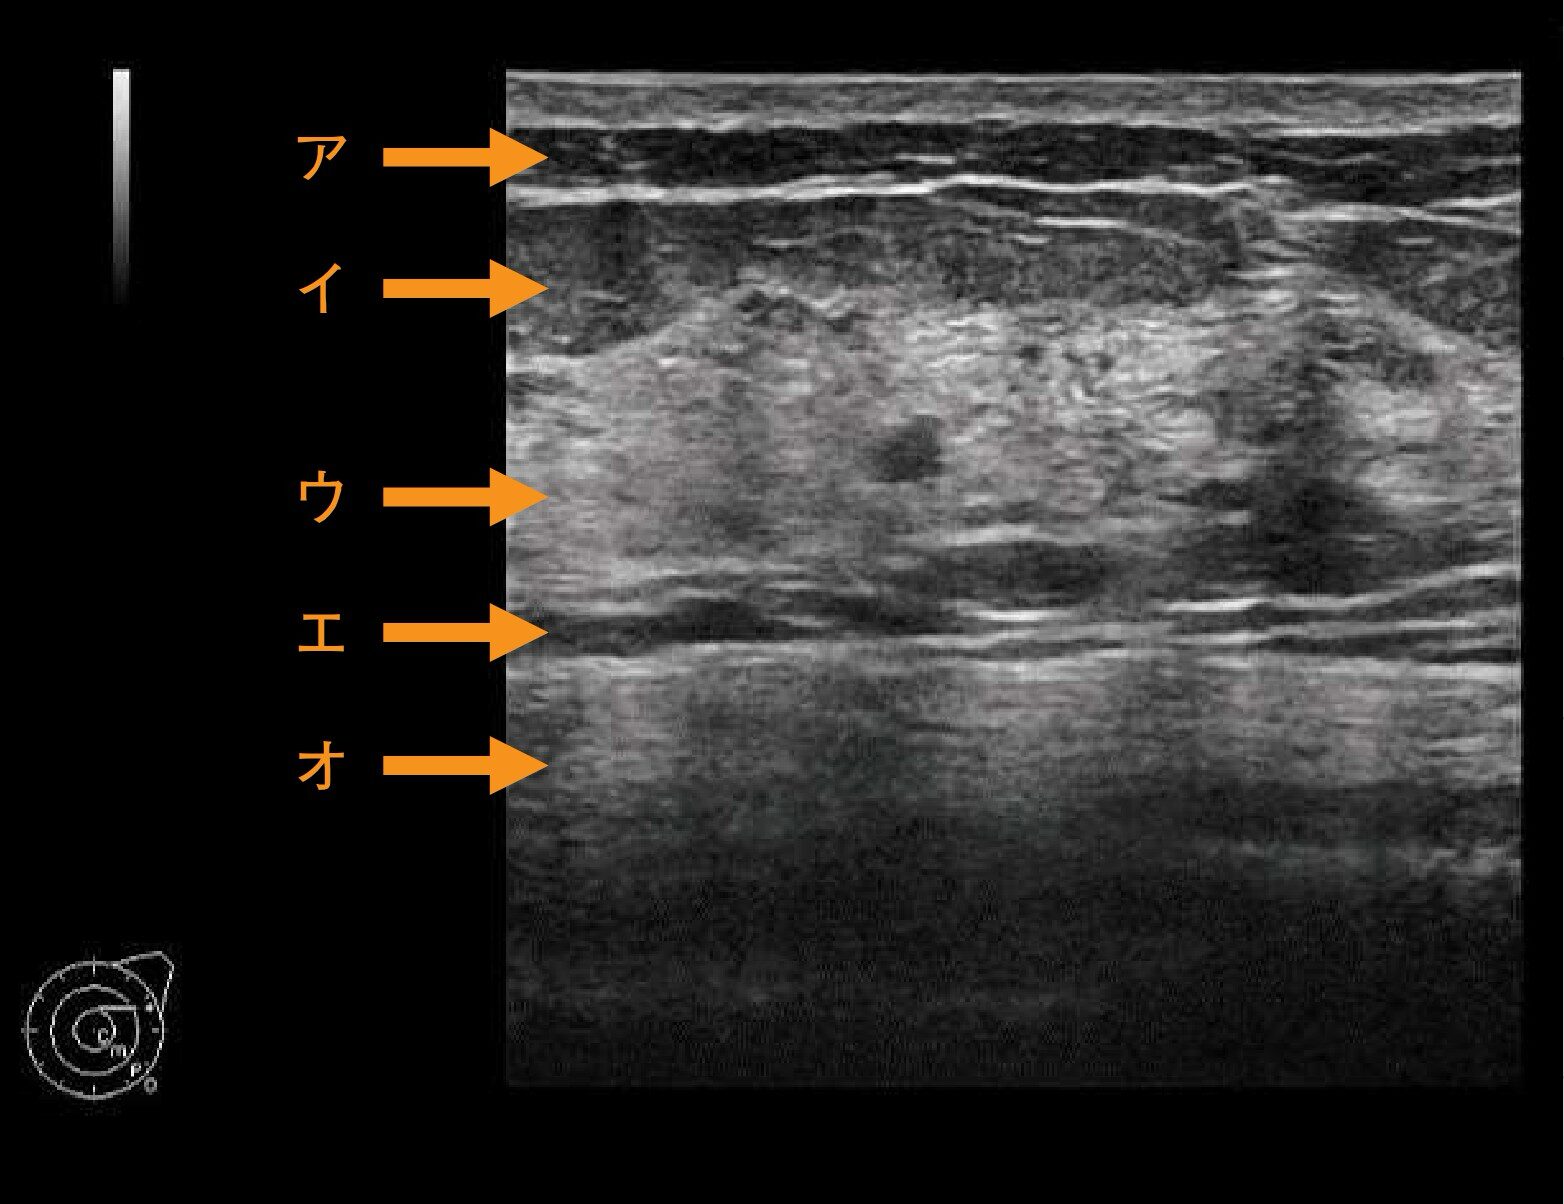

乳房超音波像(別冊No.3)を別に示す。乳腺組織はどれか。